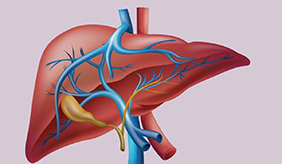

肝脏是人体最“任劳任怨”的器官之一,它每天默默完成解毒、代谢、储存营养等500多项工作。 当肝细胞内脂肪堆积超过肝重量的5%,或显微镜下30%以上的肝细胞......

查看更多>>

肝功能异常的常见症状 1、食欲减退 肝功能异常时,胆汁分泌减少会影响脂肪消化,导致食欲下降。可能出现厌油腻、进食后饱胀感。这种情况常见于慢性肝炎早期,若......

查看更多>>